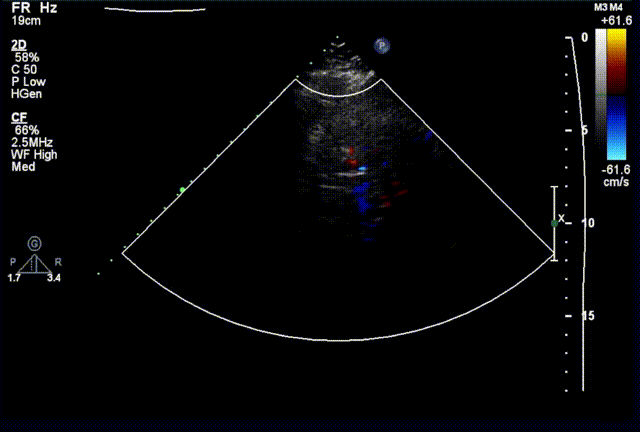

术后超声